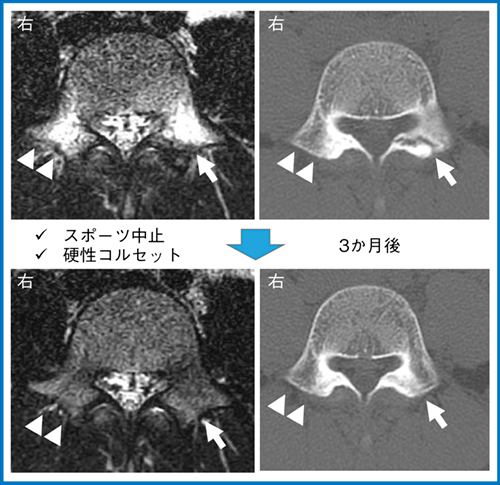

急性期腰椎分離症患者の特徴は多くの研究により明らかになっており(図1),そのような特徴を持つ患者は,MRIにて早期診断できれば高い骨癒合率が期待できる。当院では,STIR画像または脂肪抑制T2強調画像にて多レベルの椎弓根を確認できる冠状断像を撮像し,高輝度変化が認められる部位の横断像を撮像することで,明瞭に骨髄浮腫を確認し,急性期腰椎分離を早期診断している(図2)。骨癒合をめざす場合には,スポーツ活動中止とコルセット着用による腰部安静が必要である。MRIとCTの所見によりStage分類を行い,骨癒合を得られる可能性を推定し,患者と協議して治療方針を決定していく。図3は,保存治療を行った腰椎分離症の症例である。両側椎弓根に骨髄浮腫が認められ,左側(上段 ↑)は完全に分離し進行期に至っているが,右側(上段 △)は骨折線が非常に軽微な初期分離である。スポーツを中止して硬性コルセット治療を行ったところ,3か月後には椎弓根浮腫が消失し,左右とも骨癒合を得ることができていた(図3 下段)。

図3 保存治療の経過(骨癒合例)

14歳,男性,野球選手